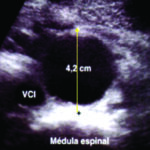

La Ecografía es el método de elección para el diagnóstico inicial, no solo por su amplia disponibilidad sino porque permite rápidamente la realización de mediciones en el plano longitudinal, anteroposterior y transverso (Fig. 26). Está indicada para la realización del screening del aneurisma de aorta abdominal en pacientes mayores de 65 años y con factores de riesgo.

La técnica de evaluación del aneurisma de aorta abdominal incluye mediciones, las cuales deben realizarse desde los bordes externos de la misma. En el plano longitudinal se examina la aorta desde el diafragma hasta la bifurcación ilíaca, y se miden el diámetro anteroposterior y la longitud del aneurisma. En el plano axial se mide el diámetro transverso. Para categorizar el tipo de aneurisma se examina la relación y distancia del aneurisma con respecto a la emergencia de la arteria mesentérica superior, de las renales y de la bifurcación ilíaca. Se examinan las arterias ilíacas y se mide su diámetro para determinar si están comprometidas. Las arterias ilíacas primitivas tienen un diámetro anteroposterior normal de hasta 11 mm (Fig 27).